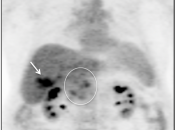

- Non-Attenuation Corrected Images

Value of NAC PET Images

- Lung Nodule Identification